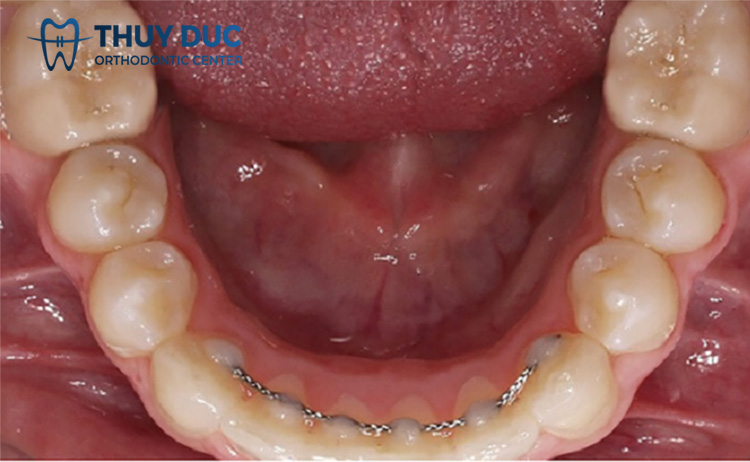

Hàm duy trì cố định có dạng một sợi dây thép mỏng hoặc sợi nhựa mềm được gắn vào mặt sau của răng, thường là trên răng cửa sau. Cũng giống như các loại hàm duy trì khác, hàm duy trì cố định có tác dụng duy trì vị trí chính xác của răng và ngăn chúng di chuyển ra khỏi vị trí đã được điều chỉnh.